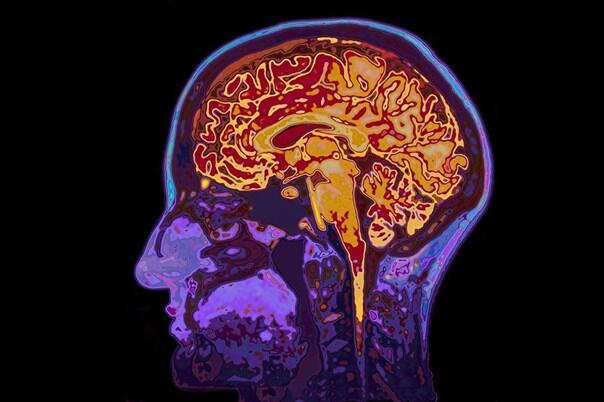

Nova studija, koja je kombinovala metode analize MRI skenova s eksperimentima na miševima, pokazala je da THC, aktivni sastojak kanabisa, smanjuje dendritičnu strukturu neurona, što dovodi do atrofije određenih regija moždane kore, posebno tokom kritičnog razdoblja razvoja mozga u adolescenciji.